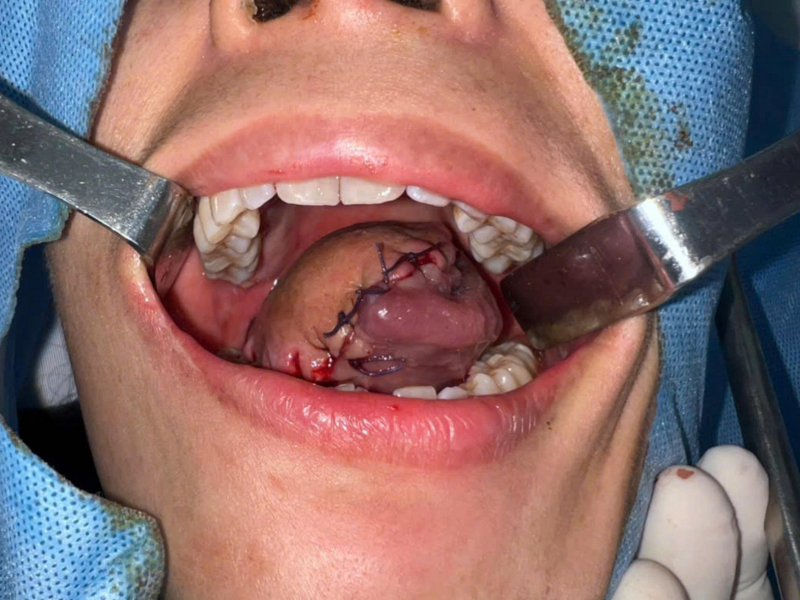

Ê-kíp phẫu thuật đã tiến hành cắt gần toàn bộ lưỡi kết hợp nạo vét hạch hai bên cổ. Do khuyết hổng sau phẫu thuật có kích thước rất lớn, các vạt tại chỗ và vạt lân cận không đáp ứng yêu cầu tạo hình, ê-kíp đã lựa chọn vi phẫu tạo hình lưỡi bằng vạt đùi trước ngoài (ALT).

Đây là phương pháp hiện đại, cho phép phục hồi cấu trúc giải phẫu với độ tương thích sinh học cao, góp phần cải thiện chức năng ăn uống và sinh hoạt cho người bệnh. Ca phẫu thuật kéo dài hơn 10 giờ, đòi hỏi kỹ thuật vi phẫu chính xác cao trong quá trình bóc tách và nối các mạch máu nhỏ dưới kính hiển vi.

Sau phẫu thuật, tình trạng bệnh nhân ổn định; vạt ghép hồng hào, ít phù nề; các vết mổ vùng cổ và đùi lành thương tốt. Chức năng vận động lưỡi cải thiện rõ, thuận lợi cho quá trình tập ăn uống và sinh hoạt hằng ngày.